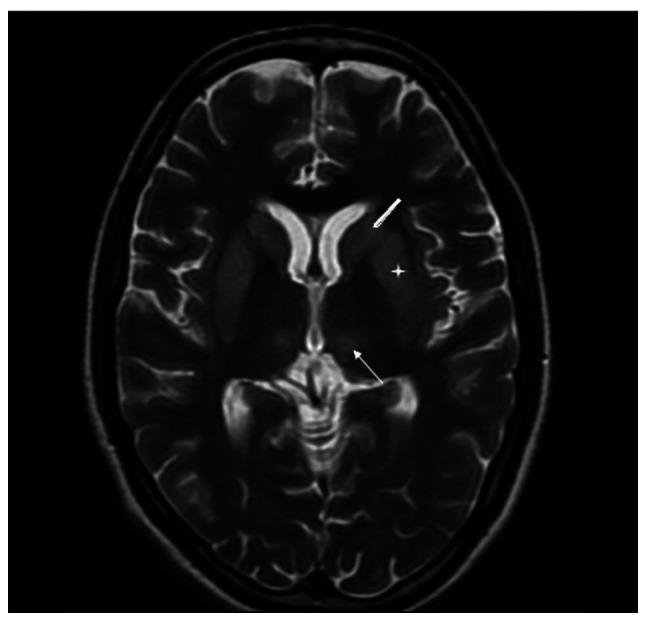

Both myxedema crisis and Sheehan's syndrome are uncommon conditions. The first-time presentation as myxedema crisis is rare in Sheehan's syndrome. The present study describes the case of a 31-year-old female patient who presented with altered sensorium in the emergency room. The patient was not a known case of hypothyroidism, but had a history of secondary amenorrhea and lactation failure following the birth of a child 11 years prior. Upon evaluation, she was found to have hypothermia, hypotension, the delayed relaxation of deep tendon reflexes, bradycardia and hyponatremia, which led to the suspicion of myxedema crisis. Her thyroid function tests were suggestive of secondary hypothyroidism and her pituitary hormonal profile revealed panhypopituitarism. The patient was managed on the lines of myxedema crisis with oral levothyroxine, hydrocortisone infusion, antibiotics and rewarming. Her clinical and biochemical parameters exhibited an improvement; however, her altered sensorium persisted. A repeat neurological examination revealed cogwheel rigidity with paraparesis, which led to the clinical suspicion of acute parkinsonism. Magnetic resonance imaging of the sella and brain was suggestive of an empty sella and extrapontine myelinolysis, substantiating the diagnosis of Sheehan's syndrome with acute parkinsonism. The patient was commenced on levodopa-carbidopa following which there was an improvement in symptoms. The patient improved over the ensuing 6 months and can now perform all household activities. On the whole, the present study indicates that the early suspicion of myxedema crisis, prompt treatment and the recognition of additional aetiology for persistent altered sensorium can result in a successful outcome for the patient.

黏液水肿危象和希恩综合征均为罕见病症。以黏液水肿危象首次发病在希恩综合征中较为罕见。本研究描述了一名31岁女性患者的病例,该患者在急诊室出现意识改变。患者既往并非已知的甲状腺功能减退病例,但有11年前分娩后继发性闭经和泌乳失败的病史。经评估,发现她体温过低、血压低、深腱反射弛缓延迟、心动过缓和低钠血症,这引发了对黏液水肿危象的怀疑。她的甲状腺功能检查提示继发性甲状腺功能减退,垂体激素检查显示全垂体功能减退。该患者按照黏液水肿危象的治疗方案进行管理,给予口服左甲状腺素、氢化可的松输注、抗生素和复温治疗。她的临床和生化指标有所改善;然而,她意识改变的情况仍然存在。再次进行神经检查发现齿轮样强直伴双侧下肢轻瘫,这导致临床怀疑为急性帕金森病。蝶鞍和脑部的磁共振成像提示空蝶鞍和脑桥外髓鞘溶解,证实了希恩综合征合并急性帕金森病的诊断。患者开始服用左旋多巴 - 卡比多巴,此后症状有所改善。患者在接下来的6个月中逐渐好转,现在能够进行所有家务活动。总体而言,本研究表明,早期怀疑黏液水肿危象并及时治疗,以及识别意识持续改变的其他病因,可为患者带来成功的治疗结果。